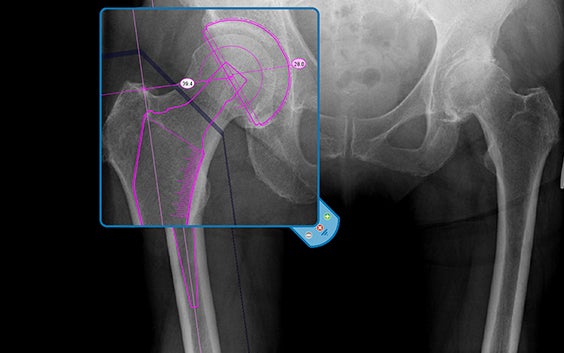

All the x-ray images were templated by Dr. Shaw using Materialise OrthoView Digital Pre-operative Planning Software. The resulting images and reports were saved back to the PACS and a copy of the templated sizes printed on what Dr. Shaw refers to as a “shopping list” or list of prostheses required. This list was used to collect the prostheses most likely to be needed for the surgery that day. In some cases, two optional sizes were recorded when the templating was between two sizes. A clinical decision was then taken at the time of surgery to identify the best option for the patient.

The component sizes recorded were stem size, stem offset, neck length for the 28 mm head, acetabular size and cement restrictor plug size. The neck length and plug sizes were roughly templated and usually two sizes were recorded on the shopping list because Dr. Shaw believes that these component sizes are best judged at the time of surgery.